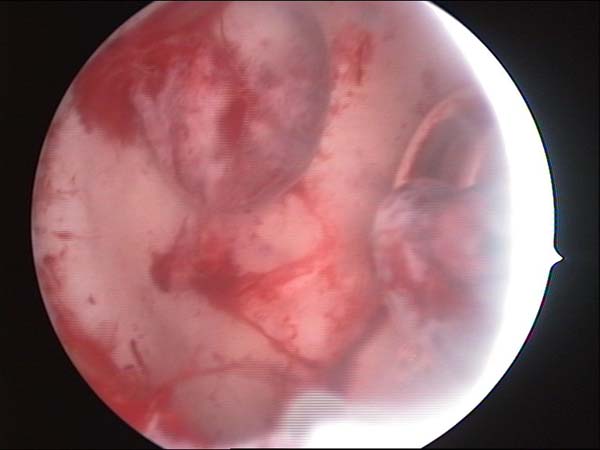

- Hysteroscopy Video clips

- Hysteroscopy Photos

Hysteroscopy Pictures | Dr N Layyous